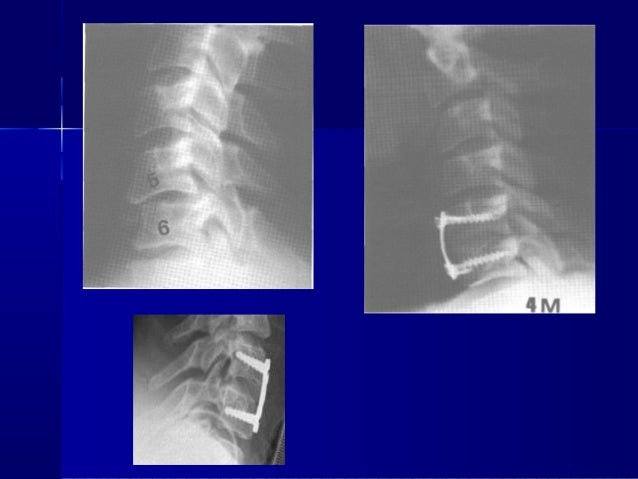

Delayed Surgical Treatment For A Traumatic Bilateral Cervical Facet Joint Dislocation Using A Posterior Anterior Approach A Case Report Journal Of Medical Case Reports Full Text

A And B Unilateral Facet Fracture Dislocation At The C4 C5 Level In A Download Scientific Diagram